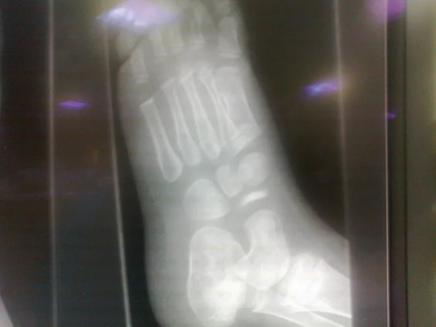

An X-ray of the affected foot was performed.

Upon careful review of the X-ray:

- The navicular bone appeared sclerotic, fragmented, hyperdense, small, and irregular.

This classic appearance leads to the diagnosis:

Köhler Disease